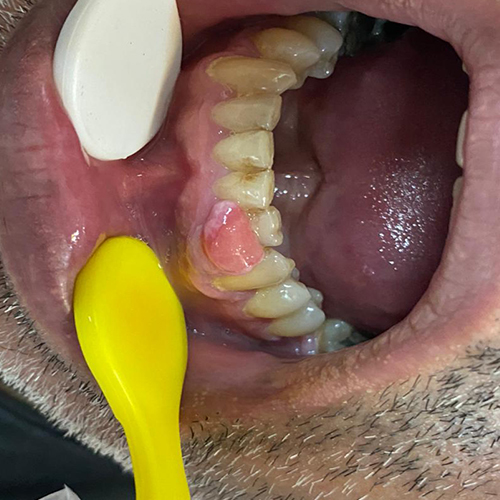

۱) پیوژنیک گرانولوما: یک ضایعه برجسته روی لثه است ( البته گاهی روی زبان و سایر مخاط هم دیده میشود) با کوچکترین دستکاری خونریزی میکند و اندازه آن شاید به چندین سانتی متر هم برسد. دلیل بروز آن شاید جرم زیر لثه باشد و شاید تغییرات هورمونی در زنان به ویژه در ایام بارداری.